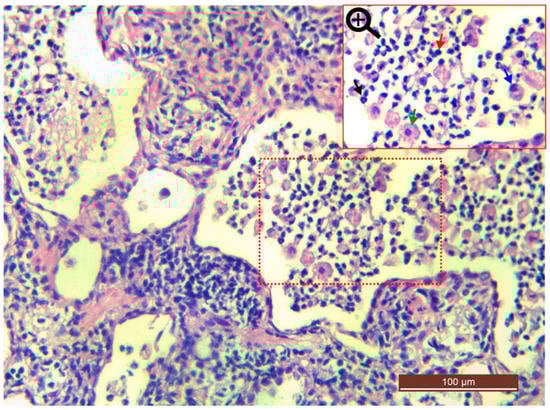

In focused bacteria cases, histopathological sections of the Cat 25 [Figure 18a–e] revealed the presence of exudate in the bronchi, bronchioles and alveoli. The exudative was comprised of a mixed population of inflammatory cells i.e., neutrophils, lymphocytes, plasma cells and macrophages, along with proteinaceous material, as shown in Figure 19. The overall examination showed that macrophages and lymphocytes were dominating cell types. The respiratory epithelium of the bronchi and bronchioles showed focal sloughing/degeneration. An area of coagulative necrosis was noticed in the lung tissue [Figure 18b]. Proliferation of type 2 pneumocytes were noticed only in a small area and most of the tissue reaction was centered on the bronchioalveolar section. On the other hand, histopathological sections of the Cat 1 and Cat 2 revealed mild and severe congestion respectively as the predominant finding with normal trachea, as shown in Figure 18f–j.

Figure 19. Bronchopneumonia due to R. equi. Photomicrograph of Cat 25 indicates exudate (combination of inflammatory cells and proteinaceous material) in the alveoli. The focused section (red dotted square) has been magnified and indicates a variety of cellularity such as macrophage (green arrow), neutrophil (black arrow), lymphocyte (red arrow) and plasma cell (blue arrow).